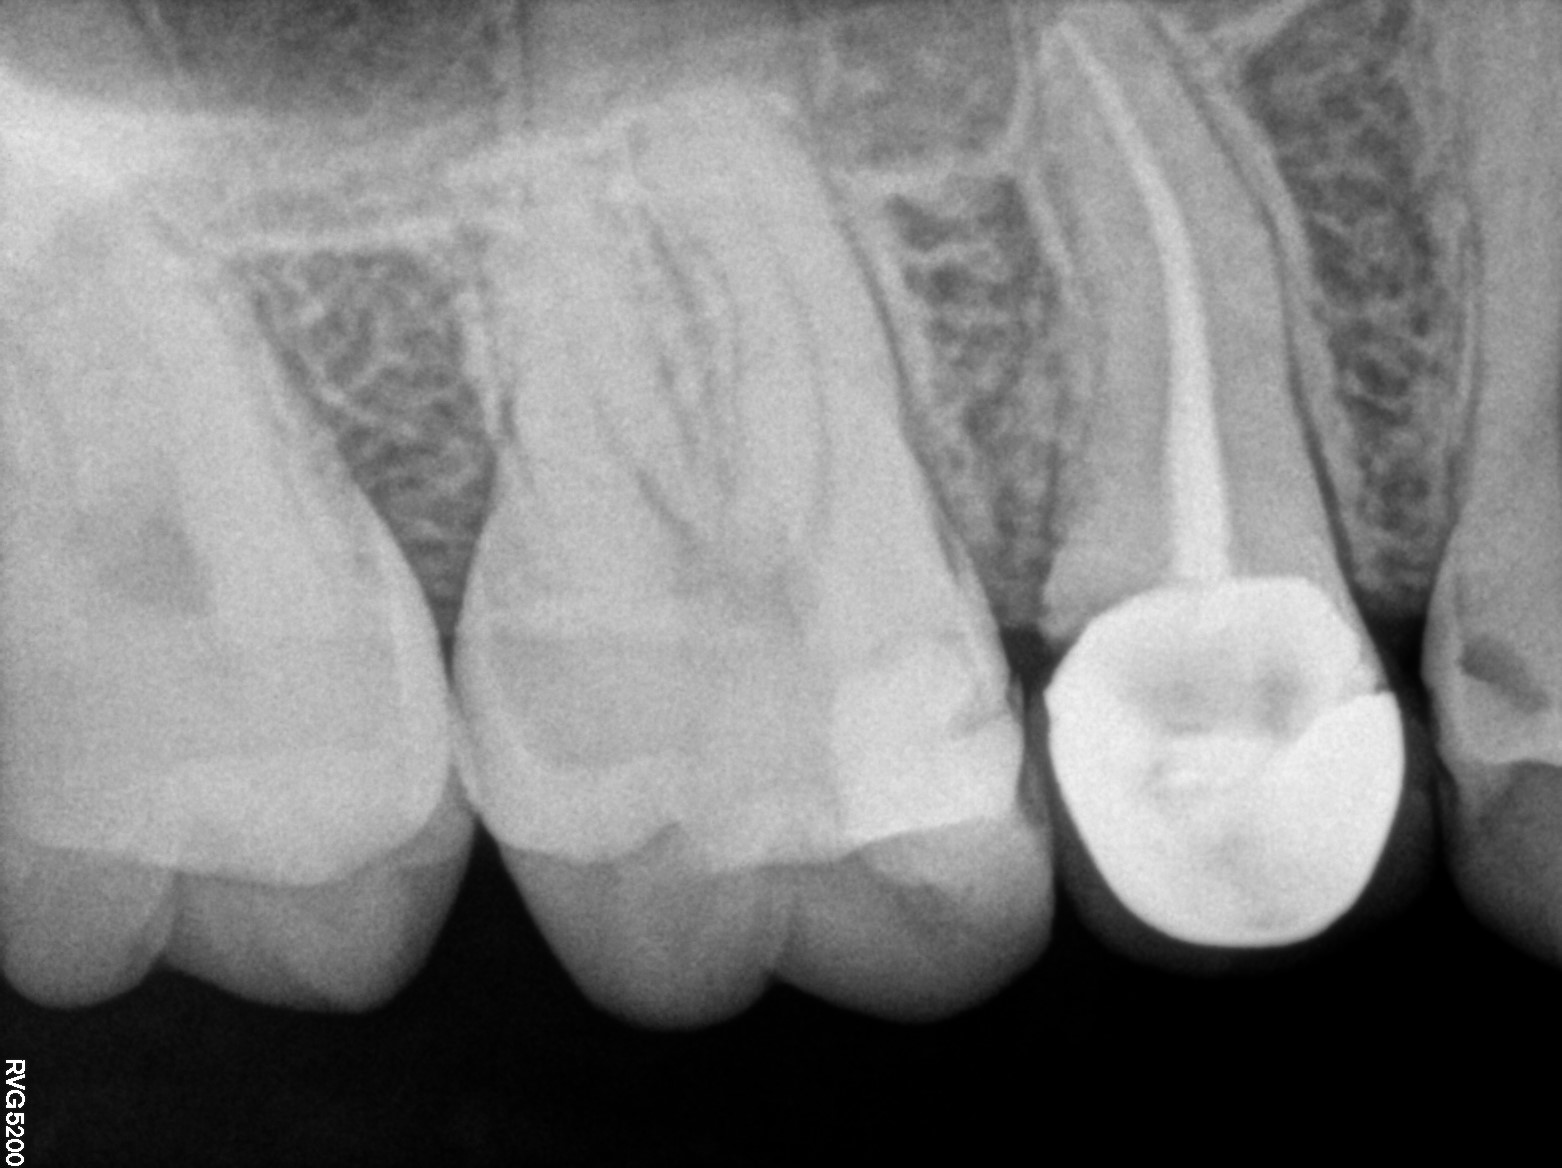

Dental Radiographs FHIR: DocumentReference · LOINC 24641-7

R5.3.jpg

24641-7